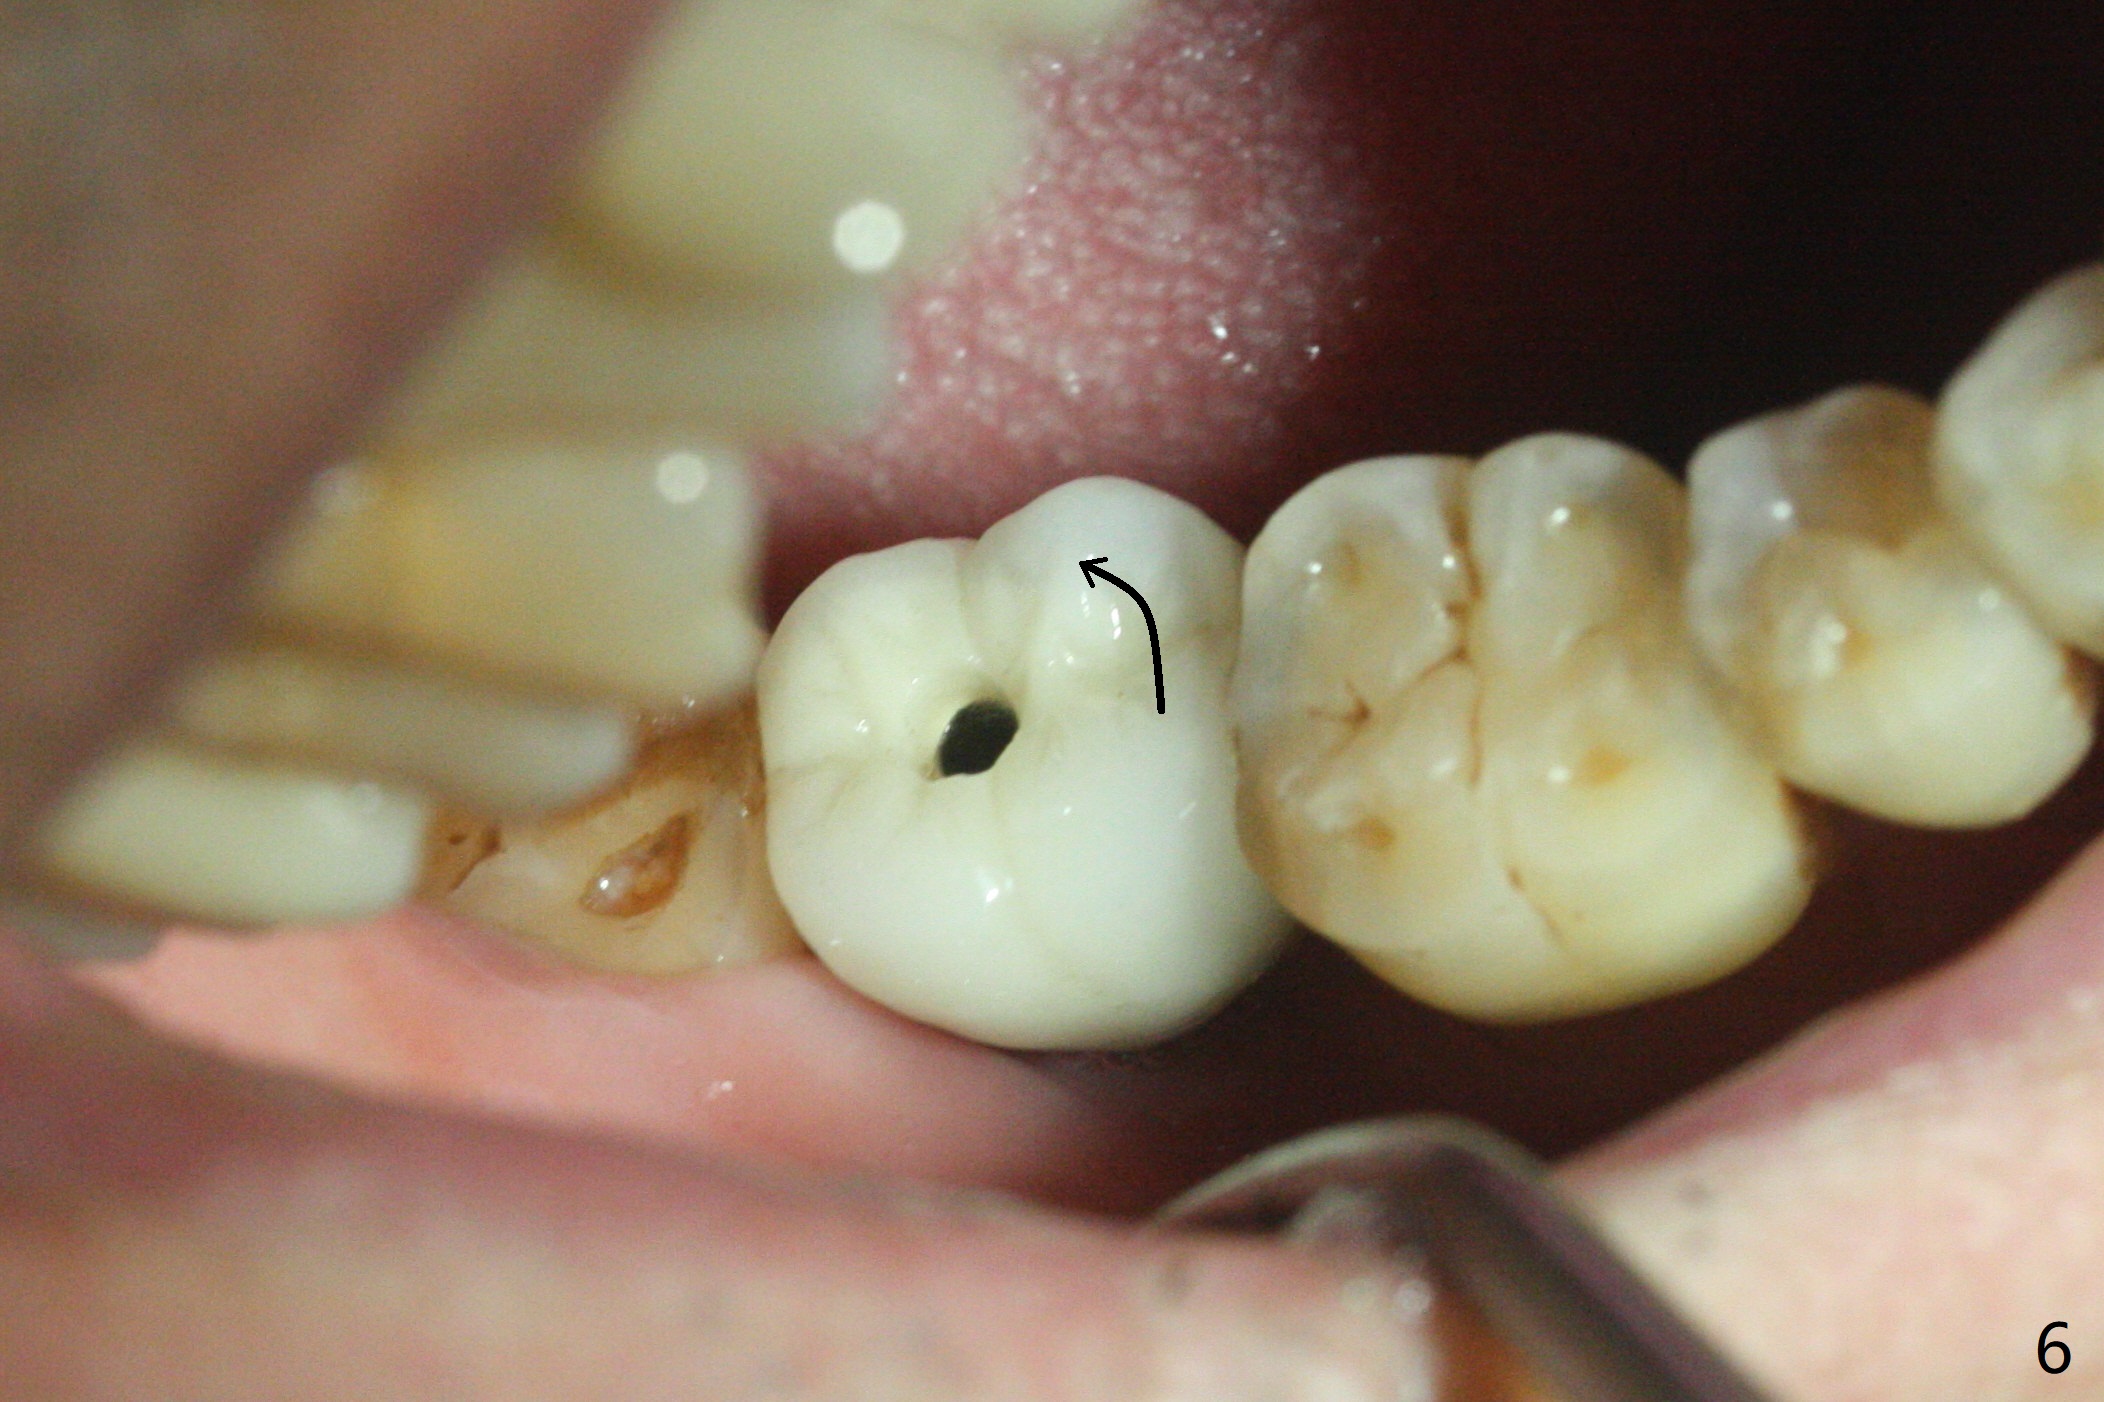

奇怪的是牙冠,基台旋转就位不需要邻面调整。就位后邻面,咬合面基本正常(说明粘固后咬合面调的很低,即使咬合低,螺丝照样松动),病人不肯进一步处理。